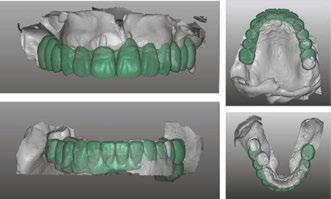

The protocol for immediate loading of fullarch implants includes the extraction of all non-salvageable teeth, implant placements, abutment placements, intraoral scans (Itero®) with scan bodies placed on the abutments, and in-house milling (Zirconzahn®) on the day of the surgery. The information referred to the esthetics, and vertical dimension is gathered with the extraoral 3D facial scans with Face Hunter software (Zirconzahn), 2D photographs, and intraoral scans prior to surgery. The day of extractions and implant surgery, abutments are placed and scanned, and initial designs are merged with anatomical landmarks. The polymethyl methacrylate (PMMA) prosthesis is milled in-house following the merging of the initial and post-implant placement digital scans and the design of the new teeth the day of the surgery.

Dr. Siranli starts by analyzing the patient’s facial esthetics to design a personalized smile and then combine 3D facial and dental scans (Figure 1).

Patient’s resting and smiling incisal display, vertical dimension of occlusion, and intraoral maximum intercuspation are evaluated clinically and through Face Hunter software (Zirconzahn®) prior to the surgery (Figures 2-4). A detailed smile design prescription gets created after this point. In this particular case presentation, the smile design prescription was:

• Bring the maxillary incisal edge down 8 mm.

• Bring the mandibular incisal edge down 4 mm.

• Bring the mandibular bone level down 5 mm.

• Labiolingually, use mandibular anterior as a guidance.

• Open the vertical dimension of occlusion 6 mm.

The day of the surgery, intraoral markers are placed, and intraoral scans are captured prior to surgery. The remaining teeth are extracted, implants and muti-unit abutments (Neodent®, Straumann) are placed (Figure 5), and abutment scan bodies

Figure 1: Face Hunter 3D facial scans merged with intraoral scans. Green color represents the new digital design of the smile design Figures 2-4: 2. Resting incisal display. 3. Smiling incisal display. 4. Maximum intercuspation Figure 5: Implants, multi-unit abutments, and scan bodies placed Figure 6: Post-surgery intraoral scans

get connected. Intraoral scans are done again after the surgery (Figure 6), and pre- and post-surgery scans are overlapped to mill the PMMA teeth the day of the surgery. While I do own a 3D printer, I like milled PMMAs more since that provides more shade options with the lighter colors. I also find milled PMMAs are stronger than the printed PMMAs.

PMMA gets milled (Figure 7) and delivered the day of the surgery with a very passive fit (Figures 8 and 9).